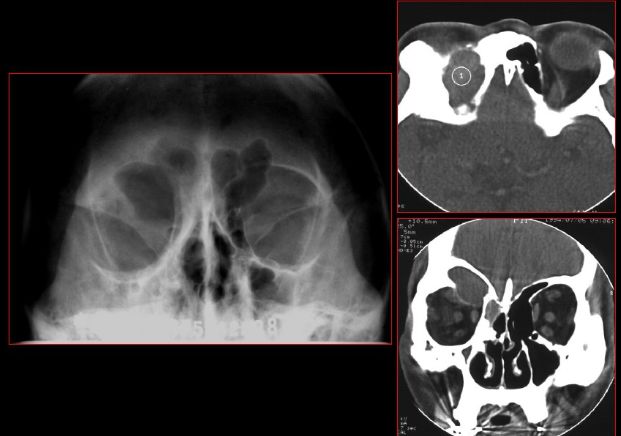

急性鼻窦炎

筛窦异物伴急性感染